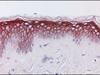

- WB, IHC

- IHC:Immunohistochemistry

C4.4A is known to be present in the placenta, skin, esophagus and peripheral mononuclear cells in humans. It is a GPI (glycosylphosphatidylinoditol) binding protein which has a similar structure to urokinase receptor (uPAR) and belongs to Ly-6 family as uPAR. While most of Ly-6 family molecules are consisted of single domain, uPAR is of three cysteine-rich domains. C4.4A is a membrane protein which binds to cell membrane in GPI binding site, and is consisted of two cysteine-rich domains and a cysteine lacking third domain.

C4.4A was isolated from metastatic rat pancreatic cancer cell lines in 1989, and its human homolog was isolated in 2001. In human malignant tumors, it has been reported that C4.4A is expressed in malignant melanoma, urothelial, lung, esophageal and colon cancer. It is considered that C4.4A mediates invasion and metastasis of cancer cells by binding with laminin and degrading extracellular matrix in the progress of cancer. Therefore, immunological detection of C4.4A in cancerous tissue is expected to be an indicator of tumor metastasis.